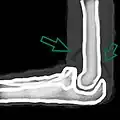

Skyline view of the patella demonstrating a large joint effusion as marked by the arrow. -